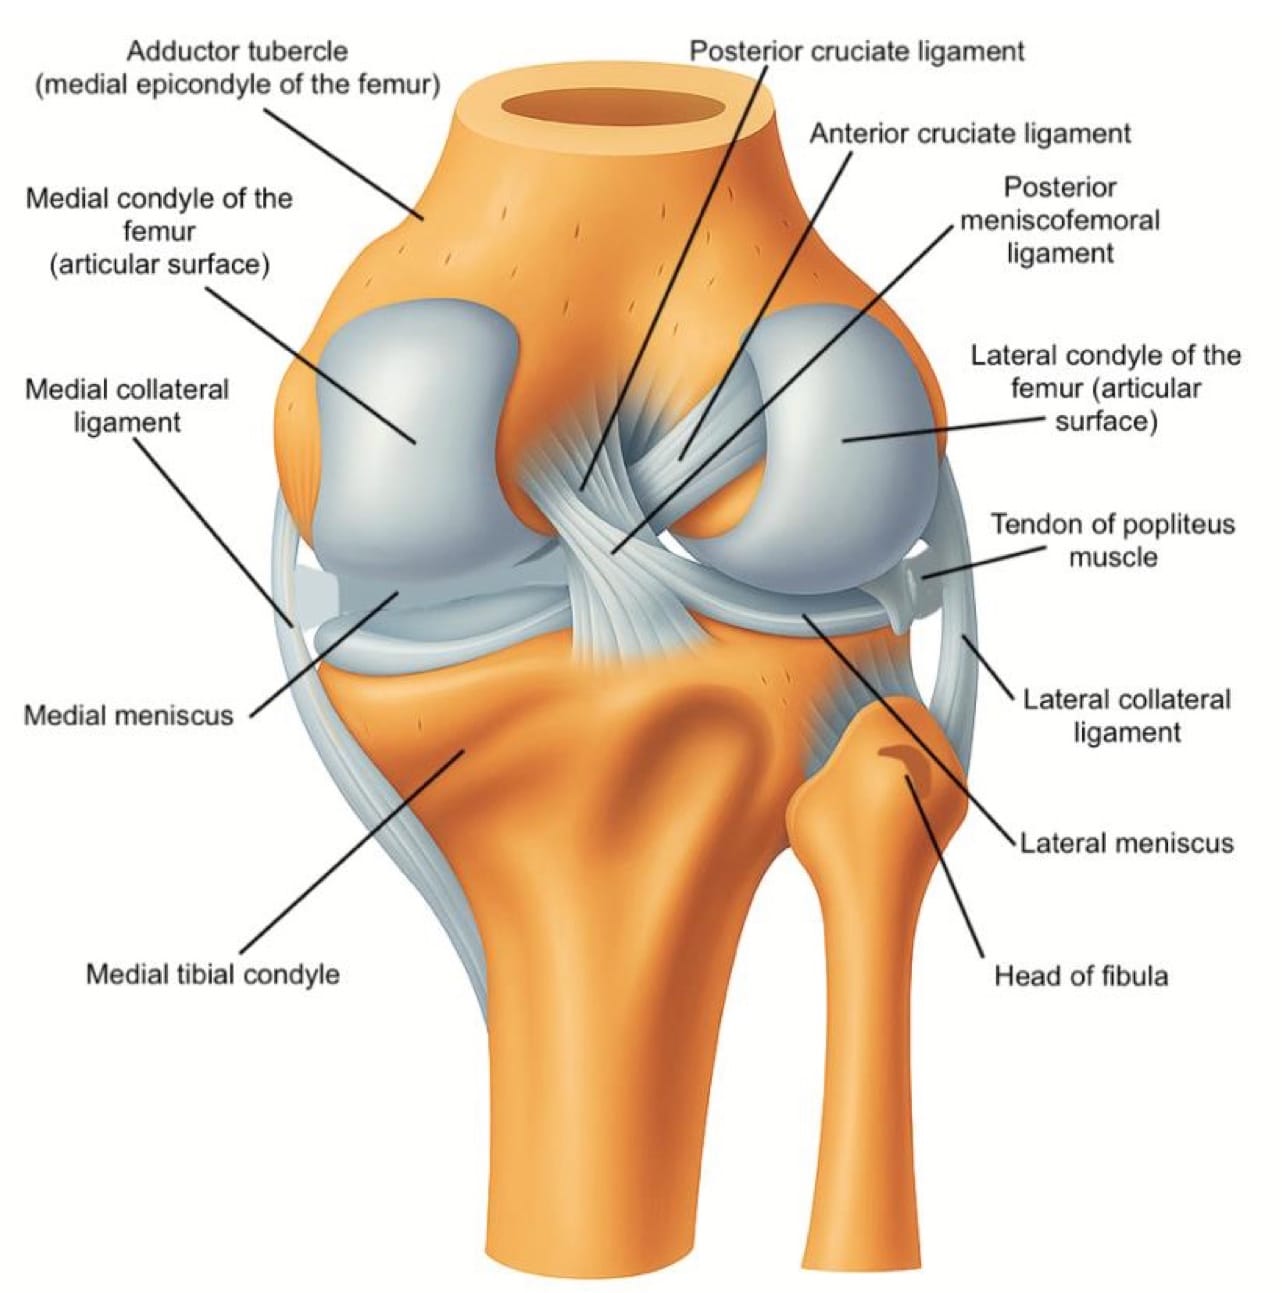

Medial Knee

Begin at “home base” by palpating the adductor tubercle on the femur and placing the transducer in long axis over this landmark, scanning distally toward the medial joint line to evaluate the MCL, which inserts proximally at the tubercle and distally on the tibia (refer to figure 2). The MCL should appear as a thin, homogeneous, hypoechoic to mildly hyperechoic, fibrillar band (refer to figure 6C); dynamic valgus stress at 20–30° flexion can help demonstrate fiber laxity or discontinuity in cases of a sprain or tear.

At the medial joint line, identify the femur superiorly and tibia inferiorly as bony landmarks. Sweep posteriorly and anteriorly along the joint line to assess the medial meniscus, looking for hypoechoic clefts, adjacent fluid, or parameniscal cysts suggestive of tear or extrusion (refer to Figure 6C).

Key Structures: Medial collateral ligament (MCL), medial meniscus, pes anserine tendons/bursa (Figures 6A-C).

Lateral Knee

Start at “home base” by palpating Gerdy’s tubercle on the lateral tibia and the lateral femoral condyle, then place the transducer between these landmarks to identify the IT band as it courses superficially toward its distal insertion at Gerdy’s tubercle (refer to figure 7 and figure 3).

Trace the IT band proximally in long axis over the lateral femoral condyle, then rotate into short axis to scan anteriorly and posteriorly, with attention to focal thickening or fluid collection. Returning to the joint line, visualize the lateral femoral condyle superiorly and tibial plateau inferiorly as landmarks, then sweep anteriorly and posteriorly to evaluate the lateral meniscus for extrusion, clefts, or parameniscal cysts (refer to figure 7).

Translate posteriorly while tilting the transducer anteriorly to optimize the visibility of the meniscus body. This action will also reveal the popliteus tendon within the femoral notch, seen as a small hyperechoic structure in the short axis. Finally, assess the LCL as a thin echogenic band extending from the lateral femoral epicondyle to the fibular head, applying varus stress to evaluate its integrity dynamically.

Key Structures: Lateral collateral ligament (LCL), iliotibial band, lateral meniscus (Figure 7 and Figure 8A).